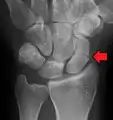

| An X-ray showing a fracture through the waist of the scaphoid | |

Scaphoid fracture

A scaphoid fracture is a break of the scaphoid bone in the wrist.[1] Symptoms generally includes pain at the base of the thumb which is worse with use of the hand.[2] The anatomic snuffbox is generally tender and swelling may occur.[2] Complications may include nonunion of the fracture, avascular necrosis of the proximal part of the bone, and arthritis.[2][1]